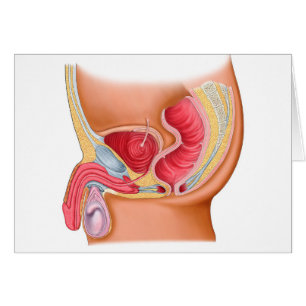

Medicinsk illustration av en Rectourethral Fistula Hälsningskort

Försäljningspris 49,00 kr. Ursprungligt pris 54,00 kr.